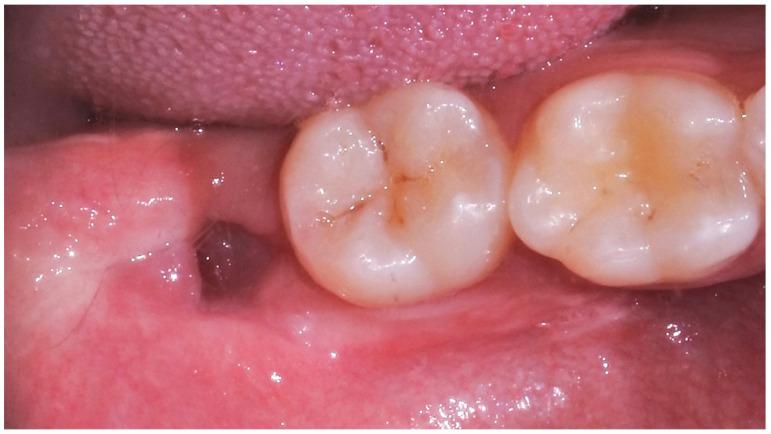

This prospective cohort study aimed to evaluate the onset and severity of pain and other complications following lower impacted third molar extraction and to identify potential risk predictors. Twenty-five patients were treated with at least one lower impacted third molar extraction. The primary outcome was the onset of post-operative pain, evaluated at 6 h, 12 h, 24 h, 48 h, 72 h, and 7 days. The secondary outcomes (trismus, edema, alveolitis, dehiscence, neuralgic injury, and suppuration) were recorded at 3, 7 and 21 days after oral surgery. A correlation analysis was performed to identify potential associations between patient- and tooth-related factors and VAS (Visual Analogue Scale) scale. When a statistically significant correlation was identified, a regression analysis was performed. Most of the patients were female (84%) with a mean age of 25 ± 3 years; the reason for oral surgery was dysodontiasis in 60% of cases, while the most frequent Pell and Gregory class was BII (36%). The VAS scale showed the onset of mild pain at 6 h (44%), 12 h (48%), 24 h (68%) and 48 (68%) after surgery. Trismus, edema, and alveolitis were observed at 3-day (20%, 64% and 12%, respectively) and at 7-day (16%, 12% and 4%, respectively) follow-up. Neuralgic injury was reported in one case (4%). The linear regression analysis showed a statistically significant association ( < 0.05) between the duration of oral surgery and VAS scores at 6 and 12 h. Finally, the binary logistic regression identified systemic disease, Pell and Gregory classification, duration of oral surgery, VAS at 6 and 12 h, trismus, and edema at 3 and 7 days as predictive factors of post-operative complications. Within their limits, the results of this study suggest that the onset of post-operative complications increases in proportion to the duration of the surgical procedure.

本前瞻性队列研究旨在评估低位阻生第三磨牙拔除术后疼痛的发生和严重程度,并确定潜在的风险预测因素。25 名患者接受了至少一次低位阻生第三磨牙拔除术。主要结局是术后疼痛的发生,在术后 6 小时、12 小时、24 小时、48 小时、72 小时和 7 天进行评估。次要结局(牙关紧闭、肿胀、牙槽炎、裂开、神经损伤和化脓)在口腔手术后第 3、7 和 21 天进行记录。对患者和牙齿相关因素与视觉模拟评分(VAS)量表之间的潜在相关性进行了相关性分析。当确定存在统计学显著相关性时,进行了回归分析。大多数患者为女性(84%),平均年龄为 25±3 岁;口腔手术的原因是阻生牙在 60%的病例中,最常见的 Pell 和 Gregory 分类为 BII(36%)。VAS 量表显示术后 6 小时(44%)、12 小时(48%)、24 小时(68%)和 48 小时(68%)出现轻度疼痛。在术后第 3 天(分别为 20%、64%和 12%)和第 7 天(分别为 16%、12%和 4%)观察到牙关紧闭、肿胀和牙槽炎。一例(4%)报告出现神经损伤。线性回归分析显示,口腔手术时间与术后 6 小时和 12 小时 VAS 评分之间存在统计学显著相关性(<0.05)。最后,二项逻辑回归确定了系统性疾病、Pell 和 Gregory 分类、口腔手术时间、术后 6 小时和 12 小时的 VAS、术后第 3 天和第 7 天的牙关紧闭和肿胀是术后并发症的预测因素。在其限制范围内,本研究的结果表明,术后并发症的发生与手术时间成正比。